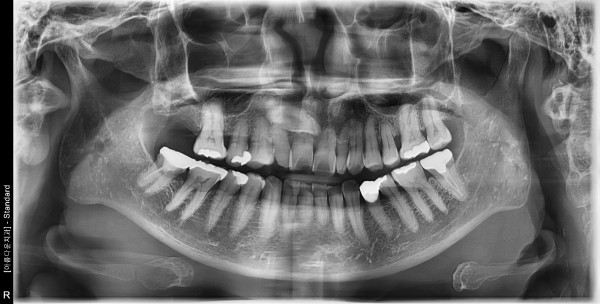

56세 여자환자 / 우측상악구치부 뼈이식 및 임플란트 식립